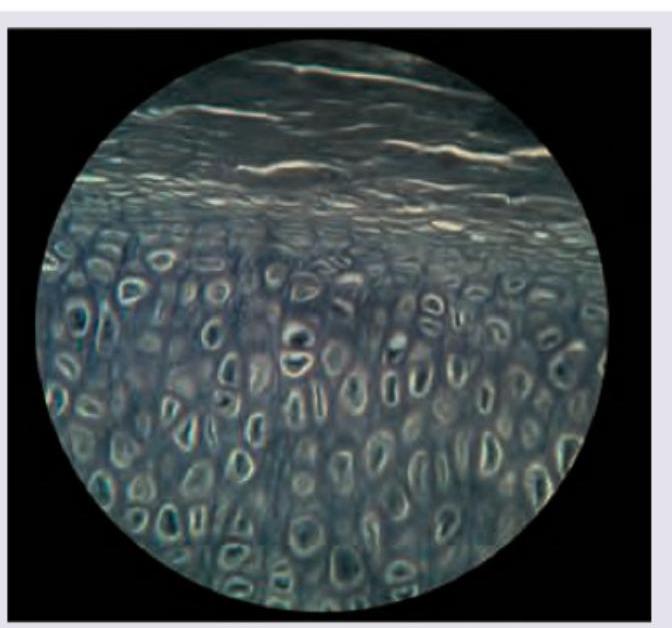

Identify the type of cartilage shown in the figure:

Explanation: ***Hyaline cartilage*** - This image displays a relatively **homogeneous, glassy matrix** with chondrocytes typically arranged in **isogenous groups** (clusters), which are characteristic features of hyaline cartilage. - The appearance of the matrix is generally smooth and devoid of prominent fibers, distinguishing it from other types of cartilage. *Elastic cartilage* - Would show a matrix rich in **elastic fibers**, which would appear as dark, branching threads within the matrix, giving it a more fibrous and less homogeneous appearance. - Typically found in structures requiring flexibility, such as the **external ear** and epiglottis. *Fibrocartilage* - Characterized by abundant, coarse bundles of **collagen fibers** interspersed with chondrocytes, giving it a highly organized, wavy, and fibrous appearance. - Often found in areas subjected to high pressure and tensile strength, such as **intervertebral discs** and menisci. *White fibrocartilage* - This is an older terminology sometimes used interchangeably with **fibrocartilage** itself, not a separate distinct type. - The three recognized histological types of cartilage are: **hyaline, elastic, and fibrocartilage** based on their matrix composition and structural properties.